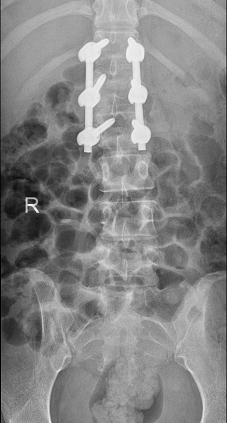

术后影像显示,螺钉位置良好